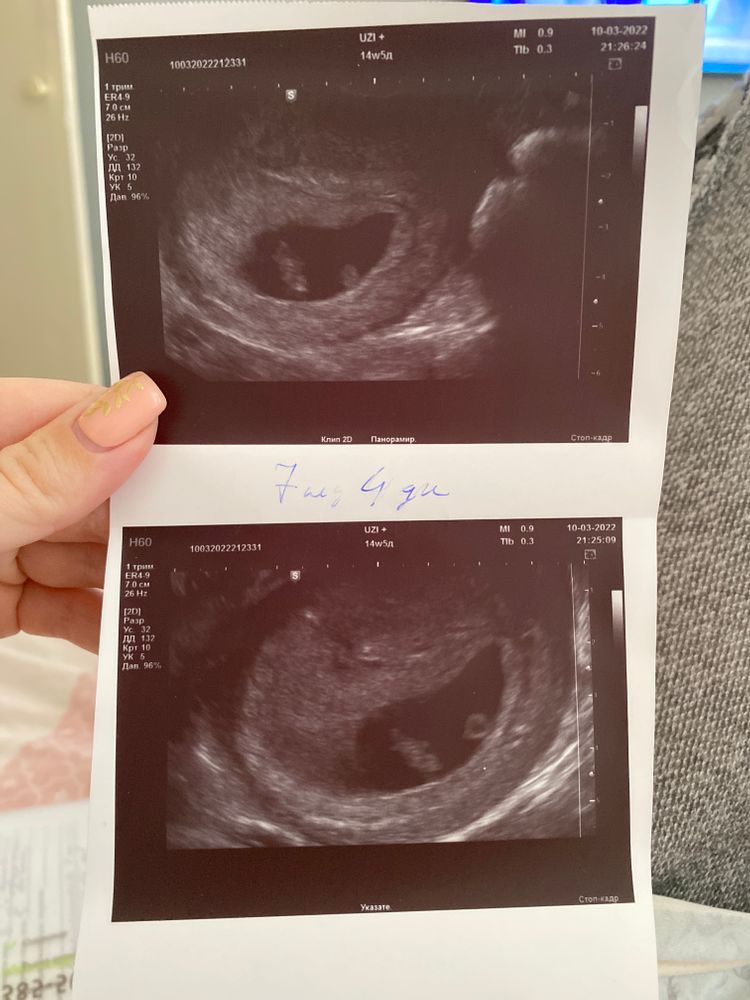

Наши первые УЗИ и вторая другая беременность 🙂

Так быстро растёт, 2 недели назад был 1мм, а сейчас уже 13мм🙀👻